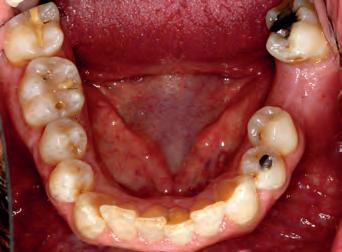

TOP ROW: Before lower occlusal, Before retracted in occlusion 2ND ROW: Before retracted left in occlusion, Before retracted left open 3RD ROW: Before retracted open, Before retracted right in occlusion 4TH ROW: Before retracted right open, Before upper occlusal